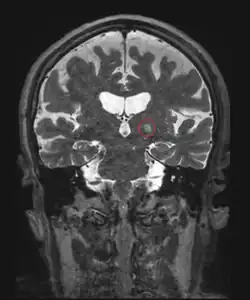

Another invasive surgical treatment of essential tremor is deep brain stimulation (DBS). DBS is a surgical procedure that involves the placement of a permanent electrode with 4-8 contacts within the brain with connecting wires connected to a pulse stimulator implanted near the patient's collarbone.[65] In the treatment of tremor, the electrodes are placed in the ventral intermediate nucleus (Vim) of the thalamus.

The pulse stimulator delivers constant electrical pulses to the target area, which interfere with activity of the target area, which has been shown to improve tremor symptoms.[91] At one year following the surgical intervention with DBS, patients showed 66% improvement and 48% improvement at 10 years.[80] DBS is considered an effective surgical treatment of ET, but there are associated side effects and complications that have been reported with DBS in clinical trials, including imbalance or gait instability, dystonia, paresthesia, hemorrhage.[79]